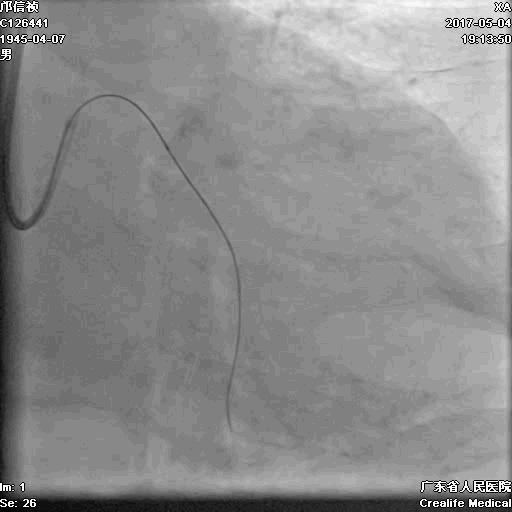

首先:IVUS指导下干预LAD

4.0mm*13mm药物支架